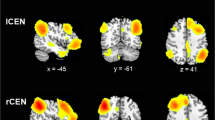

Group effect in sFCS

Figure 2a displays the brain clusters, including the bilateral precuneus, bilateral thalamus, and bilateral cerebellum (including the anterior and vermis areas) showing a significant group effect in sFCS. Post hoc analyses (Fig. 2b) showed that both the BD and MDD groups had significantly decreased sFCS in the bilateral precuneus compared to the control group. The BD group showed a significantly increased sFCS, but the MDD group showed a significantly decreased sFCS in the cerebellum compared to the control group. Moreover, the BD group showed a significantly increased sFCS in the bilateral thalamus compared to either the MDD or the control group.

Statistical results for the sFCS in the BD, MDD, and healthy controls. (a) Clusters showing significant group effects (p < 0.001 Alphasim corrected, ANCOVA). The brain surfaces were visualized using BrainNet Viewer (http://www.nitrc.org/projects/bnv/). (b) Post-hoc analyses of the sFCS for the significant clusters. The ‘BD’ type indicates that the sFCS in the cluster was specifically altered in the BD patients but not in the MDD patients. The ‘shared’ type indicates that the cluster with altered sFCS was detected in both the BD and the MDD patients. ◊, ∆, and ○ in the scatter plot indicate the mean lFCS values of a given cluster for a subject in the BD, MDD, and control groups, respectively. Red dots indicate outliers. The box plot shows the median (red line), interquartile range (blue lines), and sample minimum and maximum values (dark lines). The horizontal lines on top indicate pairwise comparisons that survived statistical thresholds: ***p < 0.001; **p < 0.01; *p < 0.05. Abbreviations: sFCS, short-range functional connectivity strength; BD (MDD), bipolar (major depressive) disorder; B (L, R), bilateral (left, right).

In this study, we found both the BD and MDD patients showed similarly decreased sFCS in the bilateral precuneus (Fig. 2, Table 2), which suggests shared short-range functional connectivity impairments in the precuneus in both disorders. Further ROC analyses indicated that the sFCS of the precuneus could be applied as a candidate biomarker to distinguish MDD patients from controls (Table 3). Nevertheless, a larger sample size is warranted in future studies to replicate our results and to extend the generalizability of our results. These results are consistent with a recent voxel-wise R-fMRI study36, which showed decreased short-range functional connectivity in the bilateral precuneus in first-episode, drug-naive adult MDD patients. The precuneus and PCC, the major hub nodes of the DMN, are related to a wide range of cognitive functions, such as episodic memory retrieval, modulation of emotionally salient memories, self-consciousness, and visuo-spatial imagery37. Several R-fMRI studies also indicated involvement of the precuneus/PCC in mood disorders, including abnormal spontaneous activity38 and functional connectivity28, 39,40,41,42. Previous task-fMRI studies also reported abnormal activity in the precuneus/PCC in BD and MDD patients during cognitive and emotional tasks43,44,45. Furthermore, other studies found normalized function in the precuneus/PCC in depressive patients following treatment with antidepressant medications46 or cognitive behavioral therapy47. Taken together, the finding of decreased sFCS in the precuneus suggests that disturbed functional connectivity in the precuneus/PCC could partially contribute to impaired integration of emotion and memory in BD and MDD patients in a depressive episode.

Although the cerebellum is primarily thought to modulate movement, in fact regions of the cerebellum are closely interconnected with the frontal cortices and limbic system48, suggesting that it plays a role in the regulation of emotion, affect, and cognitive processes49, 50. This study identified increased lFCS and sFCS in the BD patients, but decreased lFCS and sFCS in the MDD patients in the cerebellum (including the anterior, posterior, and vermis) (Figs 1 and 2, Table 2), suggesting altered functional connectivity in the cerebellum in both disorders. These results are in line with two recent studies, which also found reduced FCS in the cerebellum in MDD patients with a history of childhood maltreatment18 and increased FCS in the anterior lobe of the cerebellum in BD patients51, but these two studies did not classify the FCS into short-range and long-range FCS. Cerebellar abnormalities have been reported in both BD and MDD patients, including abnormalities of gray matter volume11, 50, 52, functional activity28, 38, 50, functional connectivity28, 53, and glucose metabolism54, 55. In addition, we observed that the lFCS of the cerebellum was associated with the number of episodes and duration of illness in the BD patients (Fig. 3). Although a longitudinal study will be needed to reach a definitive conclusion, this finding would be compatible with a post-onset, time-dependent progression of the brain changes in BD56. Taken together, our finding of an abnormal cerebellum provides additional evidence for the involvement of cerebellar dysfunction in the pathophysiology of BD and MDD.

We also detected increased sFCS in the thalamus in BD in combination with increased lFCS and sFCS in the cerebellum, findings which would suggest disturbed integrity of the cerebello-thalamo-prefrontal functional connectivity in the resting-state in BD. The thalamus, as a central relay station of the brain that filters and gates sensory inputs to the cerebral cortex, is an important key node of the cerebello-thalamo-prefrontal pathway68. A recent R-fMRI study found increased functional connectivity between the orbitofrontal cortex and the thalamus in medication-free adolescents with BD69. A systematic review of fMRI studies found increased responsiveness in the thalamus in BD but not MDD using facial affect processing paradigms. Structural MRI studies found that BD patients and their unaffected first-degree relatives had smaller thalamus volumes71, 72, suggesting that such abnormalities may reflect an underlying vulnerability marker of illness in BD. Evidence from MRI studies showed that structural alteration in the cerebello-thalamo-prefrontal network was associated with neurological soft signs (NSS) in schizophrenia and related psychotic disorders, making this network a candidate for the location of cognitive dysmetria68, 73. NSS are minor neurological abnormalities that include motor, sensory, and inhibitory dysfunctions73. Previous studies found an increase in NSS in BD patients73,74,75 but not in MDD patients73. Taken together, the impairment of the cerebello-thalamo-prefrontal pathway may cause dysfunction of information transmission and functional integration, which may bring about NSS in BD.